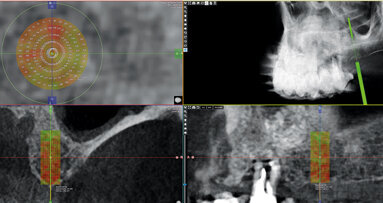

Preparace štoly pro implantát pomocí piezochirurgie nemá určitě ambici nahradit klasický způsob preparace alveolu, neboť není možné preparovat univerzálními typy implantologických koncovek pro všechny existující typy implantologických systémů. Implantologický piezochirurgický set je určen pro preparaci štoly zasahující do blízkosti průběhu nervus alveolaris inferior a dále pro preparaci v provedeném bone splitu. Pokud provedeme těmito koncovkami preparaci v laterálním úseku horní čelisti s omezenou nabídkou kostní tkáně na výšku, lze provést bezpečně i uzavřený sinus lift, neboť selektivní účinek implantologické koncovky minimalizuje riziko perforace sliznice čelistní dutiny nad štolou. Poslední indikací je preparace štoly v linguální kompaktě mandibuly. Všichni jsme se dostali do situace, kdy snaha vypreparovat štolu pro implantát v laterálním úseku mandibuly a udržet přímý směr vrtáku je zmařena v okamžiku, kdy rotační nástroj sjede do prostoru, který mu klade menší odpor – tedy do spongiózní kosti – a výsledkem je linguální sklon dlouhé osy implantátu s nutnou korekcí budoucí protetikou. Ve všech těchto situacích je ale doporučeno ukončit preparaci štoly v její kortikální části vrtákem, jehož průměr odpovídá průběru implantátu, který budeme zavádět.